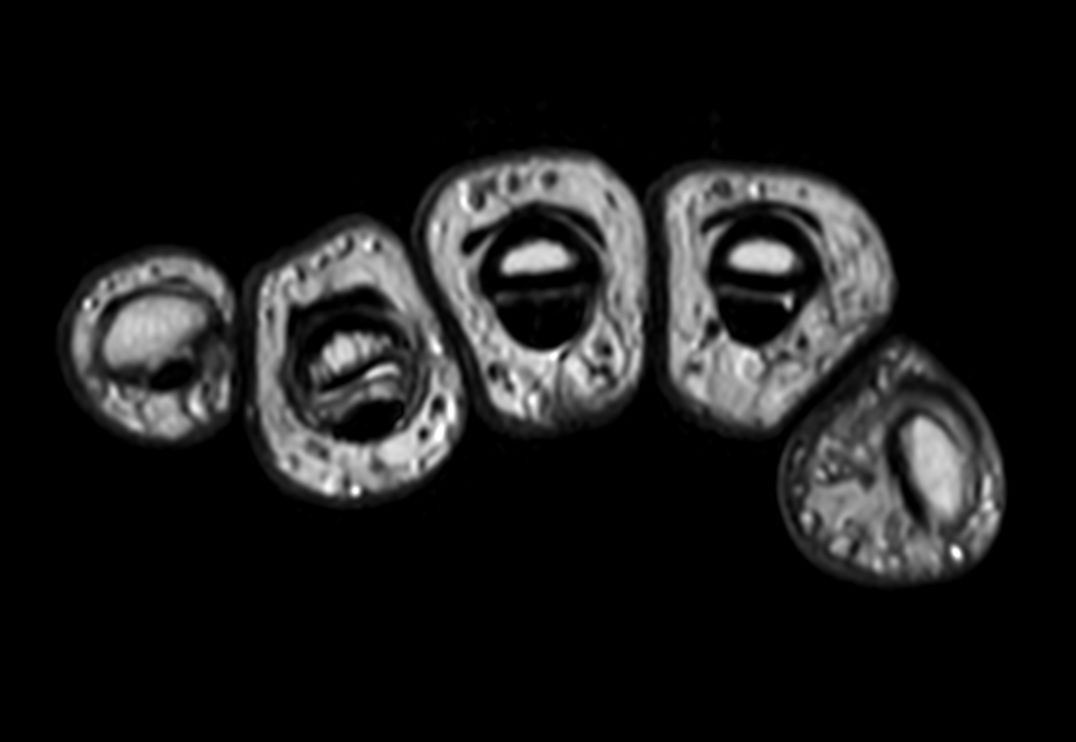

Axial T2w TSE